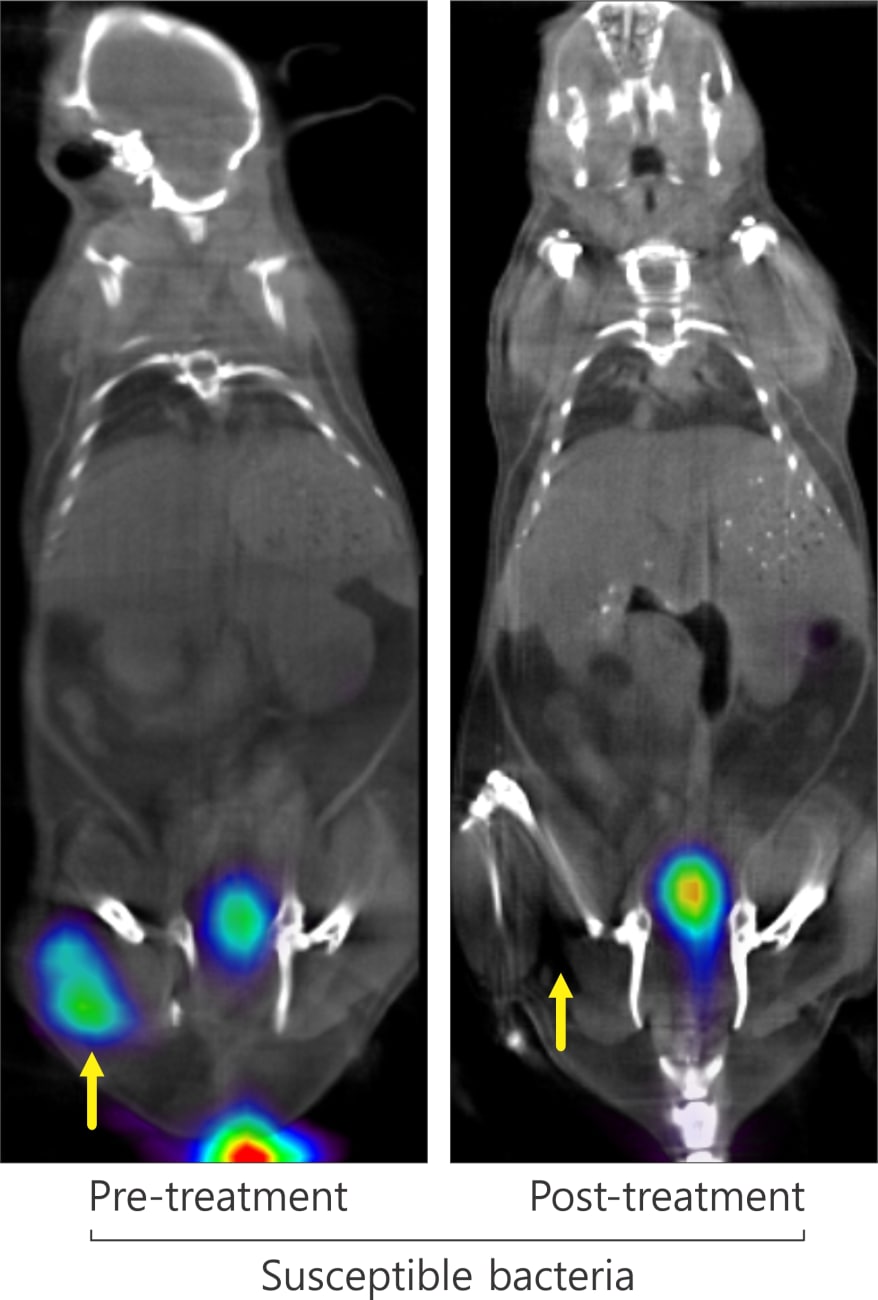

Johns Hopkins Develops New Approach to Target Bacteria Using PET How Are Pet Tracers Made The overall process of a pet‐tracer production is explained starting from the production of the radionuclide in a cyclotron, followed by the. Radioactive tracers form the basis of a variety of imaging systems, such as, pet scans, spect scans and technetium scans. The accessibility of molecular imaging probes for pet is built on 3 major pillars: • positron emission tomography. How Are Pet Tracers Made.

From clinicalconnection.hopkinsmedicine.org

Johns Hopkins Develops New Approach to Target Bacteria Using PET How Are Pet Tracers Made • positron emission tomography (pet) is a technique that measures. Radiopaedia.org provides details on pet radiotracers used in medical imaging. Radionuclide production, methodology for radiolabeling, and techniques for radiotracer production. It includes some history of pet, the basic formation of radionuclides in a cyclotron target, the processing of the precursor molecules into. Radioactive tracers form the basis of a variety. How Are Pet Tracers Made.